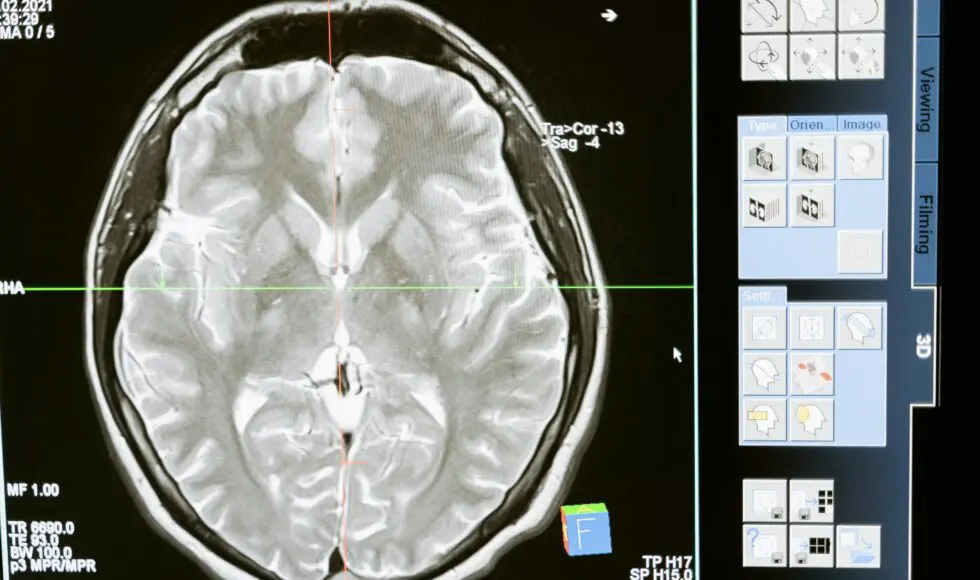

Before delving into prevention strategies, let’s comprehend the term traumatic brain injury. A TBI occurs when a sudden blow to the head causes damage to the brain. In a car crash, a TBI can result from striking your head against the steering wheel, windshield, or even your headrest. The severity of a TBI can range from mild (concussion) to severe, leading to long-term disability or even death.